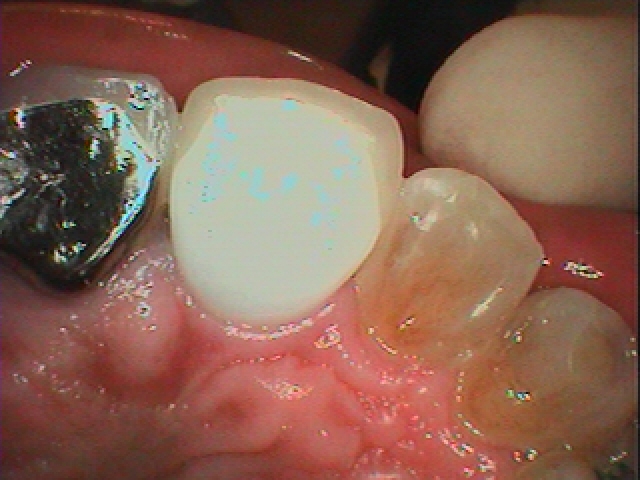

プロビジョナルからの最終ジルコニアセラミッククラウンが入るまで|お知らせ |広島市安佐南区の歯科医院 プロビジョナルからの最終ジルコニアセラミッククラウンが入るまで トップ お知らせ・ブログ お知らせ プロビジョナルからの最終ジルコニアセラミッククラウンが入るまで プロビジョナルからの最終ジルコニアセラミッククラウンが入るまで プロビジョナルになります 歯肉形態が仕上がりました 綺麗に歯肉が広がっています カスタムのアバットメントを建てていきました デンタルレントゲンになります 綺麗に歯肉形態が仕上がりました 最終ジルコニアセラミッククラウンになります 口腔内になります デンタルレントゲンになります Web診療予約 初めての方へ 選ばれ続ける理由 院内設備について 歯が痛いしみる一般歯科 歯がぐらぐらする歯周病 健康な歯を保ちたい予防歯科 子供の虫歯予防をしたい小児歯科 銀歯をセラミックに審美歯科 白い歯を目指しませんか?ホワイトニング 矯正専門医がいるので安心矯正歯科 抜けた歯を補いたいインプラント・入れ歯 医院案内 スタッフ紹介 メリィハウス歯科クリニックオフィシャルホームページ ラベンダー歯科クリニックオフィシャルホームページ お知らせ・ブログ ホーム 診療科目 一般歯科 歯周病治療 予防治療 小児歯科 審美治療 ホワイトニング 矯正歯科 入れ歯・インプラント マウスピース矯正 初めての方へ 院長・スタッフ 設備紹介 医院案内・アクセス メニューを閉じる